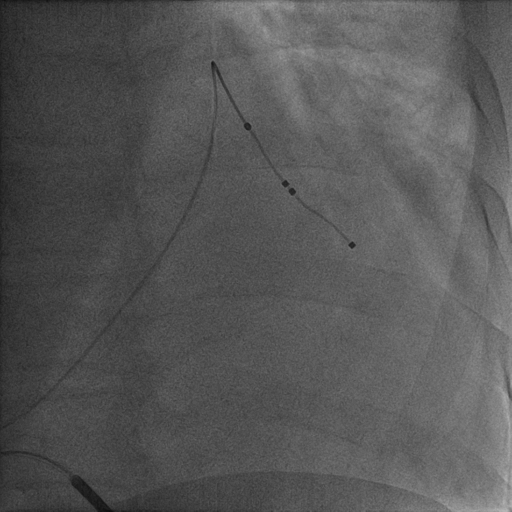

沿鞘中鞘进四极电极

最终影像